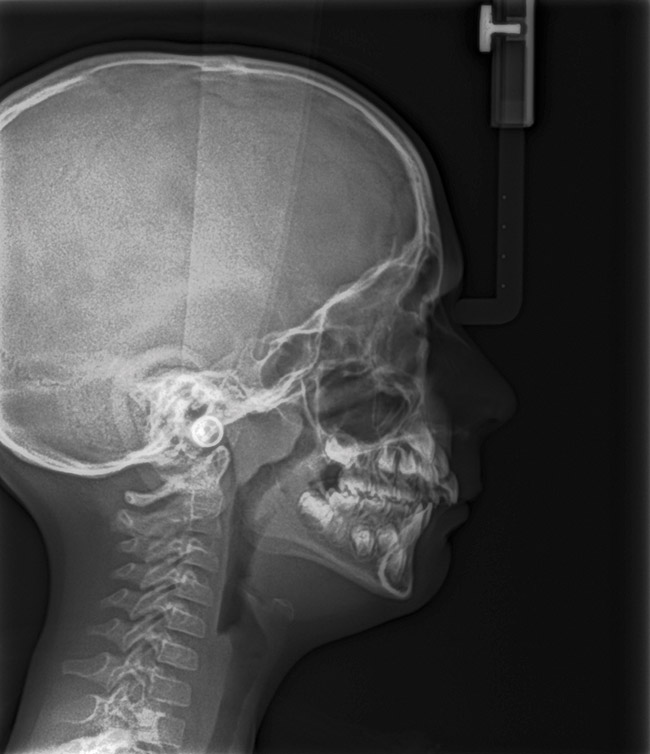

Instinctively, clinicians have concentrated on the mandible when discussing airway dimensions. However, the maxilla appears to be the more important arch in determining upper airway dimensions in OSA patients.45 The distance from A point (most posterior point in the concavity of the anterior maxilla) to Porion vertical (vertical line drawn from the most superior part of the external auditory meatus) was the most contributory cephalometric marker for airway patency. Appropriate positioning of the maxilla opens the velopharyngeal and orophayngeal airways. Additionally, proper maxillary positioning enhances mandibular growth. Thus, the lack of facial muscle activity and ideal tongue tone constrains the premaxilla, producing an abnormal airway dimension and amplifying the threat of SDB.

Tonsils and adenoids should be judged against the relative size of the airway rather than the absolute size of the lymphoid tissue46 (Figure 5 and Figure 6). Adenoids are located at the posterior of the nasal cavity on the roof of the nasopharynx (Figure 7). The normal distance from the adenoids to the soft palate for an acceptable airway should be at least 12 mm. For each millimeter decrease, the odds of the child snoring increase 1.61 times. Mouth breathers typically show a smaller upper airway dimension as well.47 The adenoid and tonsillar obstruction creates the trigger, but the deviate facial and neck muscle recruitment and tongue hypotonia cause the maldevelopment.48

The point of obstruction tends to determine the type of skeletal impact. Nasal obstruction from enlarged turbinates, blocked ostium maxillare, deviated septum, or nasal valve stenosis creates Angle occlusions of Class I, II, and III equally (Figure 8). The maxilla in these cases is positioned posteriorly and the mandible is posterior-inferior. The facial type is most commonly dolicocephalic. Blockage of the airway predominately by the adenoids will create growth patterns that yield mostly Class II occlusions and anterior open bite with both jaws located posterior-inferiorly. Facial type is again dolicocephalic with the typical long-thin “adenoidal” face49 (Figure 9 through Figure 12). If the tonsillar tissue is responsible for the airway obstruction, the tongue will have an abnormal resting posture. Class III occlusions will be more common with the maxilla normal or posterior placed (Figure 13 through 15). The tongue may direct the mandible anteriorly or, because the tongue is not in the roof of the mouth driving A point anterior, the maxilla will become bimaxillary retrusive.50 In some cases, the anterior posture of the tongue will create an open bite. This is incorrectly referred to as a tongue thrust. The impact from a thrust does not alter the tooth position. Long-term, low forces cause tooth movement. The posture of the tongue against or between the anterior teeth due to the excessive tonsillar size creates the open bite (Figure 16 and Figure 17). Facial types in this group are more brachyfacial. Lastly, if the airway is blocked through a combination of factors, the Angle classification will be either Class II or III. The maxilla will be in a normal location and the mandible will be the affected arch (Figure 18). These craniofacial changes are not restricted to OSA; all SDB will create unique alterations depending on the patient compensation. Children with UARS have been reported to display high, narrow palates, dolicofacial form, and a Class II malocclusion, indicative of largely adenoidal blockage.51

Dentists identifying craniofacial changes early in development may resolve the malocclusion by simply referring for adenotonsillectomy (T&A). The impact of T&A on the pediatric immune system is controversial. A recent 5-year longitudinal, prospective study demonstrated that adenotonsillectomy does not pose adverse short- or long-term impact on the cellular or humoral immunity.52 Cephalametric changes (eg, posterior incline to the mandible, anterior incline to the maxilla, longer anterior and shorter posterior face height, and upper and lower teeth more retroclined than a normal matched control) were detected in 5-year-old subjects with adenoid-induced OSA.53 T&A resolved the OSA in all subjects. At the 5-year recall, cephalometric evaluation demonstrated that the mandibular plane angle and incisor relationship was similar to the control. Early resolution of the SDB allowed time for the proper use of the oral-facial and tongue muscles. Closed mouth breathing with the tongue in the roof of the mouth directed ideal growth.